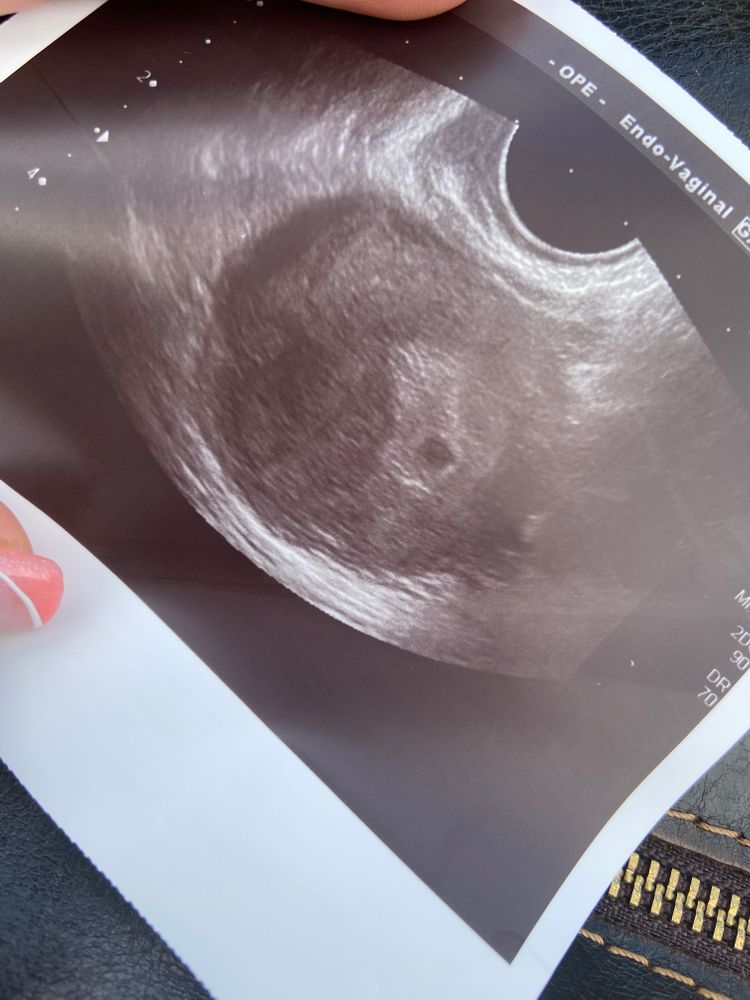

На 23 дпо тоже небыло жм, только плодное 7 мм и все

Вот мое пя на 39 день цикла (5 мм) Изображение